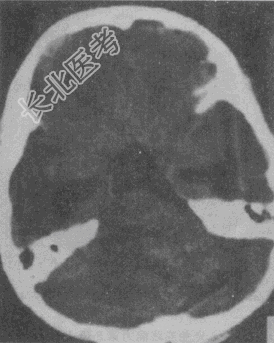

- 单项选择题女性,43岁。左侧听力下降伴左侧面部不适7个月, 根据CT图像(见图),最可能的诊断是

A、听神经瘤

B、三叉神经鞘瘤

C、脑膜瘤

D、海绵状血管瘤

E、动脉瘤